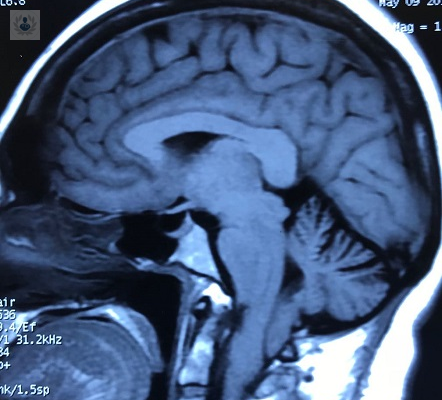

Malformación de Chiari: ¿qué es y cómo se detecta?

La malformación de Chiari es una enfermedad congénita, se presenta después de la adolescencia y hasta la etapa de adulto. El tratamiento es quirúrgico y tiene como objetivo descomprimir principalmente la unión del tallo cerebral con la médula.